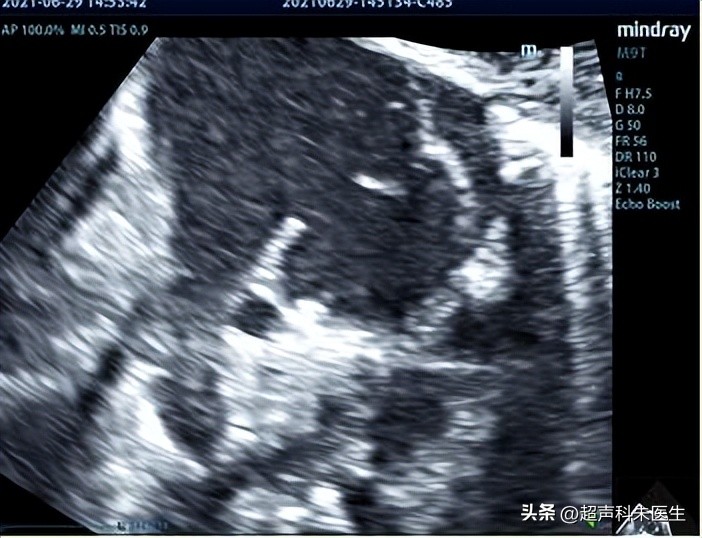

首选 超声 检查,直接征象:房间隔或冠状静脉窦顶盖的回声失落和房水平分流。

继发孔型房间隔缺损(II型)中央型:缺损位于房间隔中心位置,缺损周边可见完整的房间隔结构,有时缺损呈筛孔状。